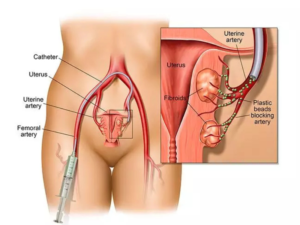

Medical advancements have made it possible to treat fibroids using image-guided techniques. These procedures are designed to target fibroids precisely without damaging surrounding tissues. One of the most commonly used methods is uterine fibroid embolization (UFE), where the blood supply to fibroids is blocked, causing them to shrink gradually.

The treatment process begins with proper evaluation using imaging tests such as ultrasound or MRI. These tests help determine the size, number, and location of fibroids. Based on this assessment, a suitable treatment plan is created.

During the procedure, a small catheter is inserted through a tiny puncture, usually in the wrist or groin area. Using real-time imaging guidance, the doctor performs the treatment with high precision. Non-Surgical Fibroid Treatment Bengaluru is typically done under local anesthesia, ensuring patient comfort throughout the procedure.